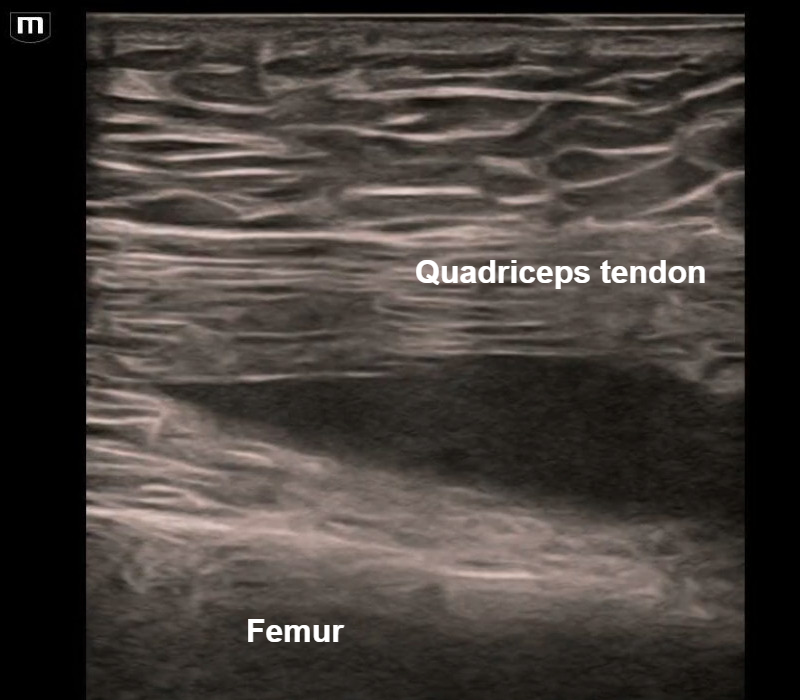

50 y/o F presented with a swollen painful knee. An ultrasound-guided arthrocentesis was performed to insert a needle and drain a suprapatellar effusion, which is seen shrinking in size as it is drained! The pain resolved and the patient went home! #POCUS #FOAMed #ultrasound